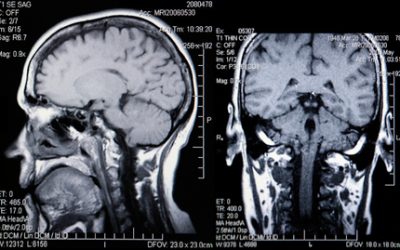

What is an MRI Scan?

If you have seen a GP or a Consultant who has advised you should have an MRI Scan, you may wonder what this involves so read on to find out more. How is an MRI Scan Different from an X-Ray? An X-Ray uses radiation to take a picture of the inside of a body. This is...